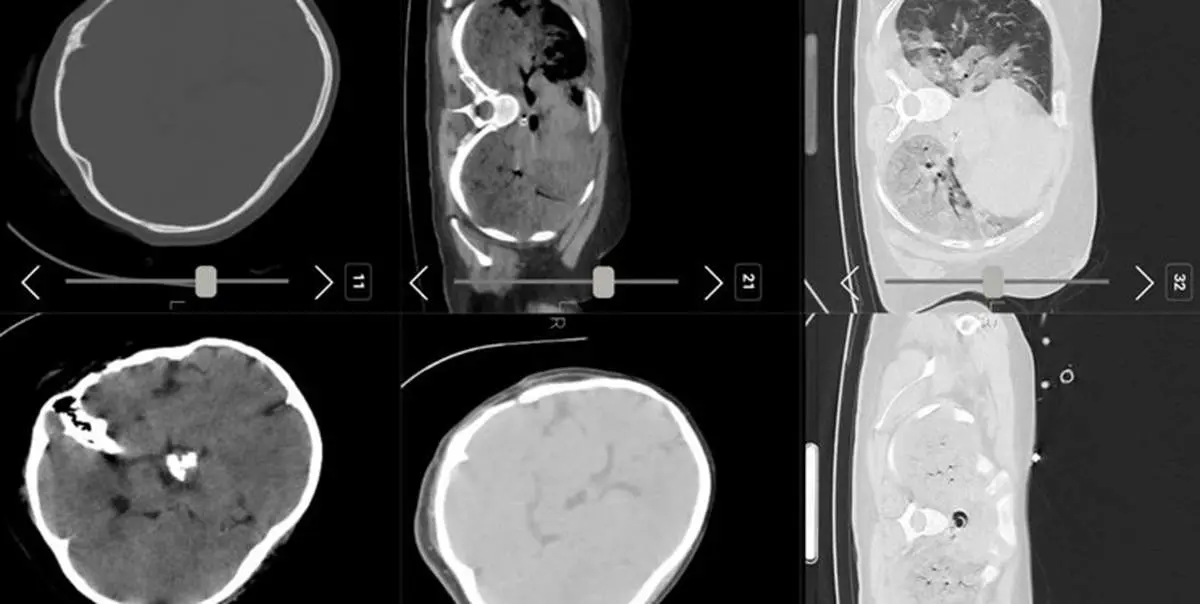

بررسی پرونده بیمار طی سال های گذشته نشان میدهد، وی به طور مکرر به متخصصان مغز و اعصاب و داروهای تجویز شده برای بیمار، احتمال ابتلای مهسا امینی به بیماری مغزی را افزایش میدهد. همچنین بررسی پرونده نشان میدهد وی طی سال گذشته چند نوبت به صورت مکرر به شهر تبریز برای درمان توسط متخصص غدد مراجعه کرده است.